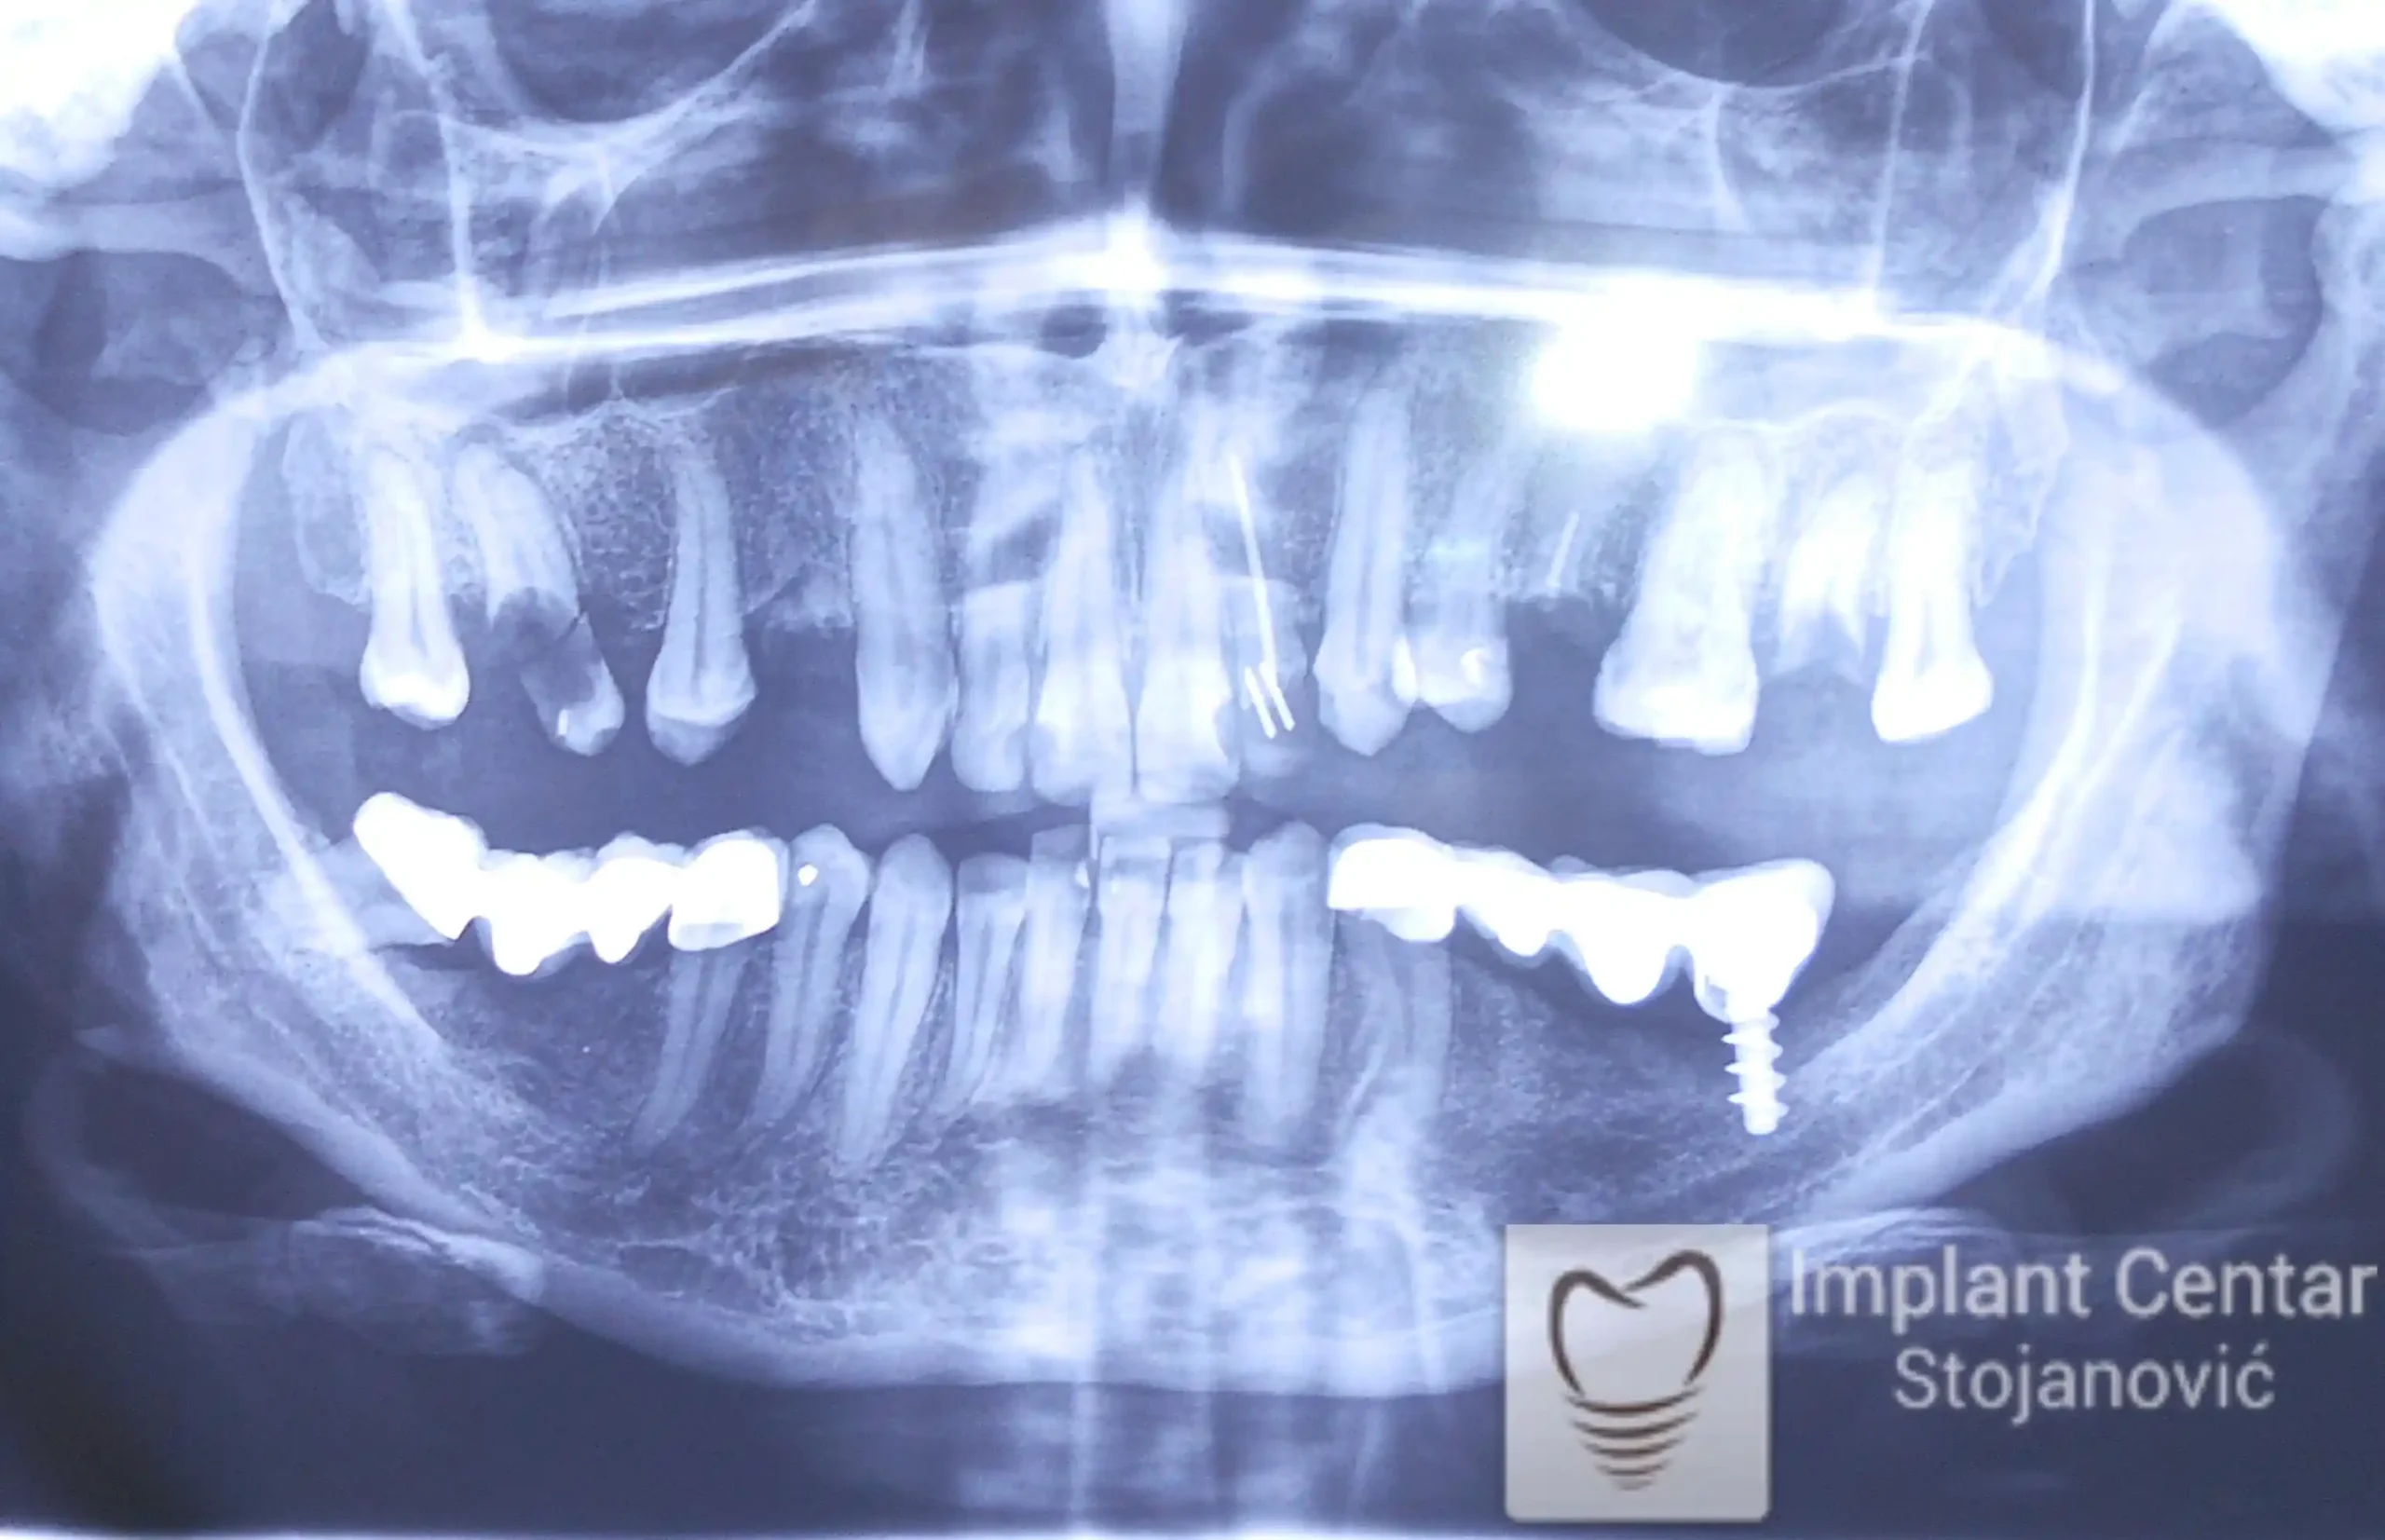

Na slici 1. i slici 2. prikazan je izgled pacijenta pre početka terapije – klinički i rendgenološki.

Nakon vađenja zuba, ugrađeni su implantati. Na slici 3 prikazan je ortopan snimak sa ugrđenim implantatima. Tokom perioda osteointegracije, pacijent je bio zbrinut fiksnim privremenim krunicama na implantatima, koje su izrađene samo dva dana nakon hirurške intervencije.